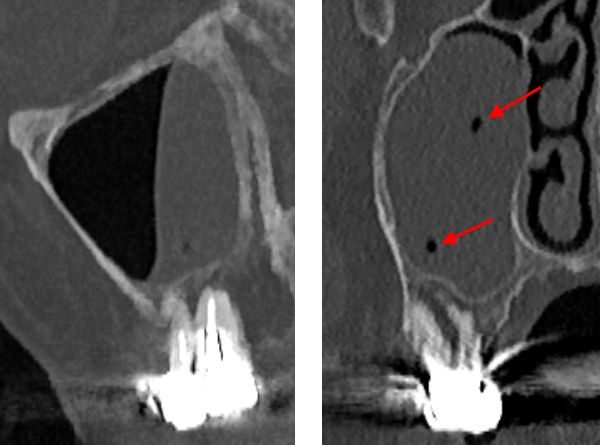

73-jährige Patientin (25.06.2021 / 404)

Das DVT zeigt, dass die Kieferhöhlenschleimhaut über den zwei verdächtigen Molaren stark angeschwollen ist. Zudem befinden sich in der Schwellung genau über den beiden wurzelbehandelten Molaren zwei kleine rundliche Aufhellungen. Das könnten Mikroabszesse sein, die von Bakterien in den Wurzelspitzen verursacht werden.

Aber erst die zwei kleinen Mikroabszesse in der Schleimhaut (rote Pfeile) konnten

die Patientin motivieren, den 16 zu extrahieren.

Nach der Extraktion wurde der 16 zur Reinigung eine Stunde lang in NaOCl (1%) gelegt. Da erschienen bei der palatinalen und bukkomesialen Wurzelspitze zwei offene Wurzelkanäle! Diese haben wahrscheinlich schon seit Jahren eine ganz kleine Menge Bakterien beherbergt.

▶ Der Wurzelkanal der bukkodistalen Wurzel (bd) ist biologisch perfekt verschlossen.

▶ Die Wurzelkanal der bukkomesialen Wurzel (bm) ist etwa 0.2 mm weit offen und wäre ohne die

Wurzelbehandlung noch kleiner geworden.

▶ Die palatinale Wurzel (pal) wurde instrumentell erweitert (kreisrunde Form) und dann mit

AH26 gefüllt. Das AH26 ist dann aber verschwunden. Es hat eine dunkle Verfärbung hinterlassen

und einen Platz für Bakterien freigegeben, welche die Sinusschleimhaut entzünden konnten.

Keine Wurzelfüllung kann den Apex so perfekt verschliessen wie der Nerv selber bei dieser bukkodistalen Wurzel (bd). Mit den Jahren werden Tausende von Bakterien im Blut an den apikalen Leerräumen der wurzelbehandelten Zähne (bm und pal) vorbeigeschwemmt.